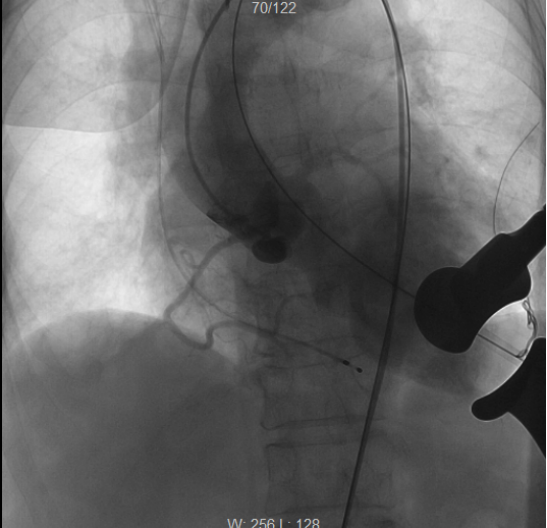

术前造影,提示主动脉瓣在舒张期出现大量返流